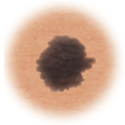

Melanoma: Signs

The first sign of melanoma is often a change in a mole, or the appearance of a new mole. These ABCDE rule can help you tell a normal mole from one that might be melanoma. The ABCDE rule is:

| Melanoma | Sign | Characteristic |

|

| Asymmetry | When half of the mole does not match the other half  |

| Border | When the borders (edges) of the mole are ragged or irregular  |

| Color | When the color of the mole varies throughout  |

| Diameter | If the mole's diameter is larger than a pencil's eraser  |

| Evolving | Changes in the way the mole looks over time  |